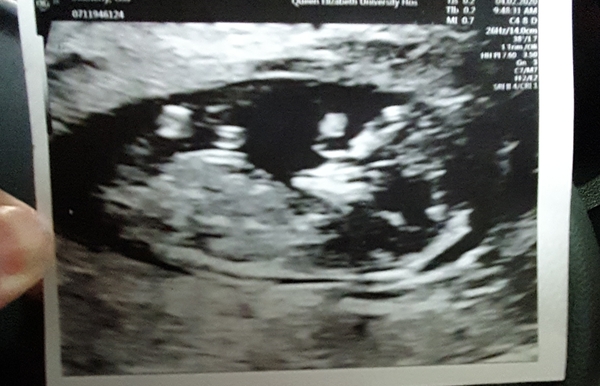

Mine from my 12 week scan a few weeks ago!!

Looks like we may all be getting there now!!